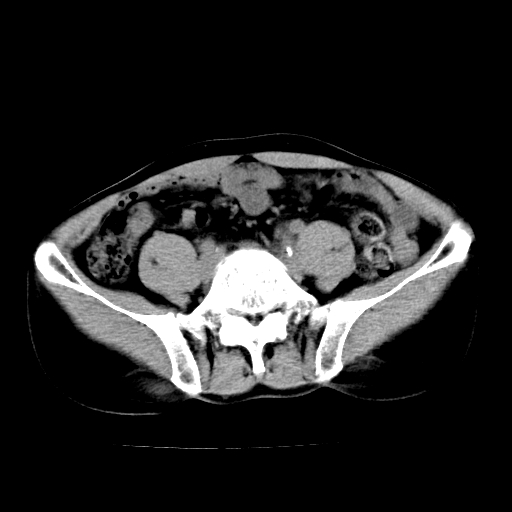

男,47岁,左输尿管结石碎石治疗后10余日。彩超示:左输尿管下段狭窄、输尿管积水。请各位讨论一下左输尿管下段结石还是静脉石?

象是第二狭窄处结石伴以上输尿管、肾盂轻度积水。

输尿管结石伴以上输尿管、肾盂轻度积水。

两侧髂总动脉壁斑状及点状钙化.左侧输尿管行经与左髂总动脉相交后见高密度影,且下段输尿管管腔未见扩张,应该要考虑结石伴以上输尿管及肾盂积水.但右侧结节状高密度影,也应该是结石吧!那以上输尿管未见扩张呢!因此静脉结石可能性也较大.请问楼主碎石前左侧输尿管结石位置.

虽左侧有轻度肾盂积水但不支持结石。1结石边周应该有软组织包绕呈晕征。2钙化点前面见输尿管影也不支持是结石。3彩超没提结石。建议超生复查。

输尿管先位于腹部,后进入盆腔,最后斜穿膀胱壁开口于膀胱,因此,临床上常将输尿管分为腹段、盆段和壁内段。第1个狭窄:在肾盂与输尿管移行处。第2个狭窄:在跨过髂血管处。第3个狭窄:在穿过膀胱壁处。这些狭窄是结石容易滞留的部位。

左侧输尿管有轻度扩张伴有肾盂积水,输尿管下段周围的高密度影不象在输尿管内。

同意,不支持结石。(因显示该高密度影前见扩张输尿管影,另外两侧对称显示)。

左侧高密度影在左侧输尿管的内侧方,所以不考虑输尿管结石.

我认为不是结石的可能性大,因为他的位置和血管钙化的位置邻近